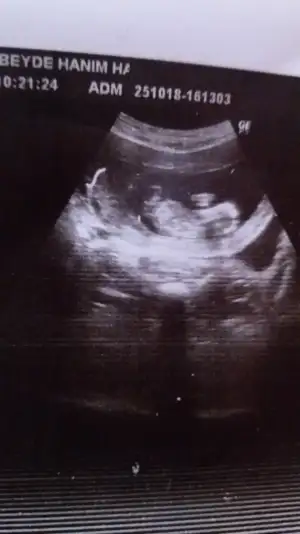

bizim usg fotomiza benziyo bebek sola yakin. hadi insallah.

karindan cekilmis bu foto. kalp atis hizini soyledimi doktorun ?

Nubtan anlayan varsa fotoya yorum yapabilir mi 11hafta 5 gunluk olmus

• Screenshot_2018-11-07-10-56-32.webp

Screenshot_2018-11-07-10-56-32.webp

26,9 KB · Görüntüleme: 89